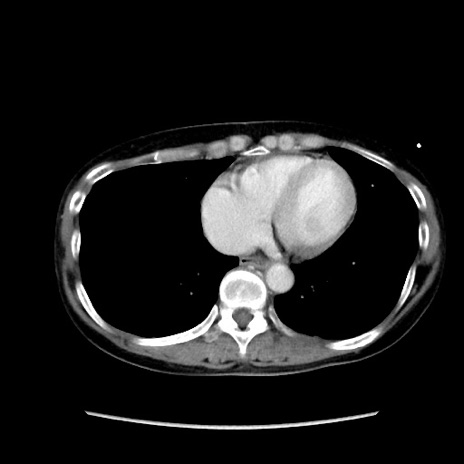

症例32(横断像)

【症例】40歳代 女性

【主訴】上腹部痛、嘔気・嘔吐

【現病歴】約9時間前頃から急に上腹部痛、嘔気、嘔吐が出現。改善しないため救急要請。

【既往歴】子宮頚癌(広汎子宮全摘術、放射線療法)、腸閉塞

【身体所見】腹部:平坦、軟、腸雑音亢進、上腹部を中心に腹部全体に圧痛あり。

【データ】WBC 8400、CRP 0.03